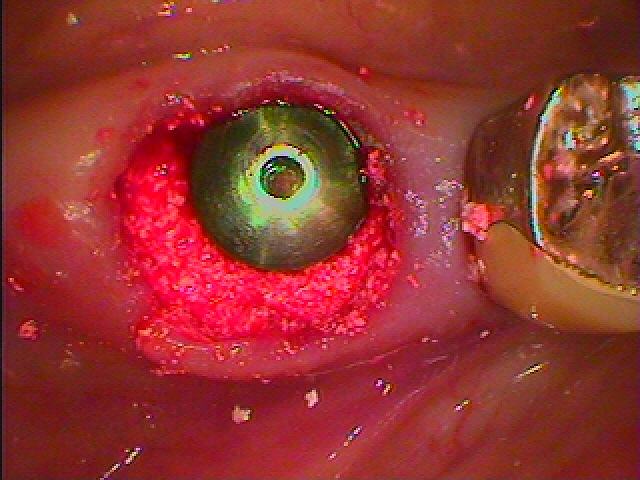

歯肉も腫れています

状態がよい時に抜歯即時インプラント埋入をさせていただきます